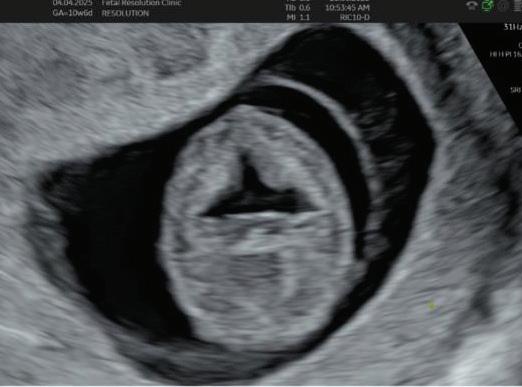

1. EARLY PREGNANCY SCAN (6–10 WEEKS)

Findings:

• Gestational sac at ~4.5–5 weeks-Appears as anechoic fluid filled structure surrounded by a decidual reaction (Double Decidual sac sign).

• Measure Mean sac diameter .

• Yolk sac appear around ~5–5.5 weeks.

• Embryo with cardiac activity around 6 weeks.

2. NUCHAL TRANSLUCENCY (NT) SCAN

• Done @11–13+6 weeks.

• CRL 45–84 mm.

• This is the cornerstone of first trimester screening.